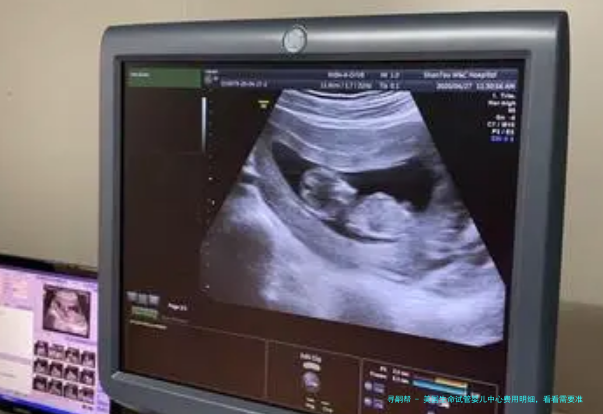

2、超声波监测

⑴医疗设备:美国生命试管婴儿中心配备了世界上最前沿的医疗设备,囊括超声波监测、卵巢穿刺手术等。

| 超声波监测 | $1,000 |